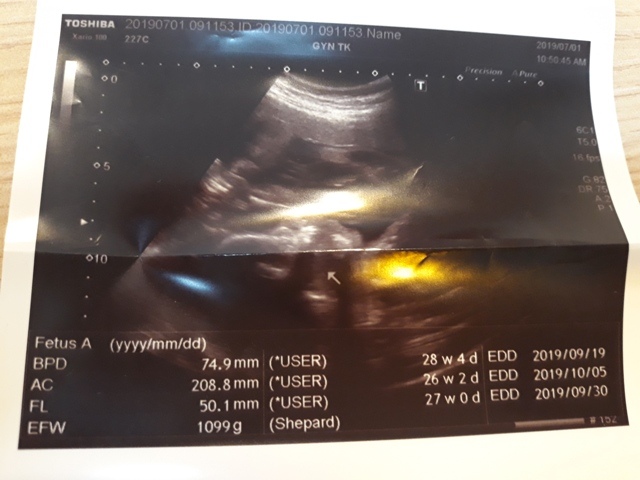

妊娠糖尿病數值為124,超過140就是超標,小純的妊娠糖尿病檢驗結果為正常的數值。接著,去照超音波,自從05月22日和06月03日的產檢,發現小飛的FL(腿長)比實際天數少一個星期後,讓小純感到很鬱悶,他最近很努力的吃鈣片,希望能讓小飛的腿長趕上進 度,今天一量,27週又0天,雖然還是落後實際的天數(27週又3天),但已漸漸趕上了。

27週又3天↓

近六次產檢資料統計

| 日期/項目 | BPD | AC | FL | EFW | 心跳 |

| 2019年03月04日 | 無資料 | 無資料 | 無資料 | 無資料 | 無資料 |

| 2019年04月01日 | 28.9mm | 77.9mm | 14.2mm | 107g | 153 |

| 2019年04月29日 | 41.7mm(44%) | 125.7mm(61%) | 28.9mm(103%) | 241g(125%) | 150 |

| 2019年05月22日 | 53.4mm(28%) | 160.6mm(28%) | 34.6mm(20%) | 408g(69%) | 150 |

| 2019年06月03日 | 58.3mm(9%) | 179.6mm(12%) | 38.2mm(10%) | 584g(43%) | 157 |

| 2019年07月01日 | 74.9mm(28%) | 208.8mm(16%) | 50.1mm(31%) | 1099g(88%) | 141 |

| BPD:胎兒頭骨橫徑 AC:胎兒腹圍的長度 FL:胎兒大腿骨的長度 EFW:胎兒的體重 括弧內百分比為較上次產檢的成長比例 | |||||